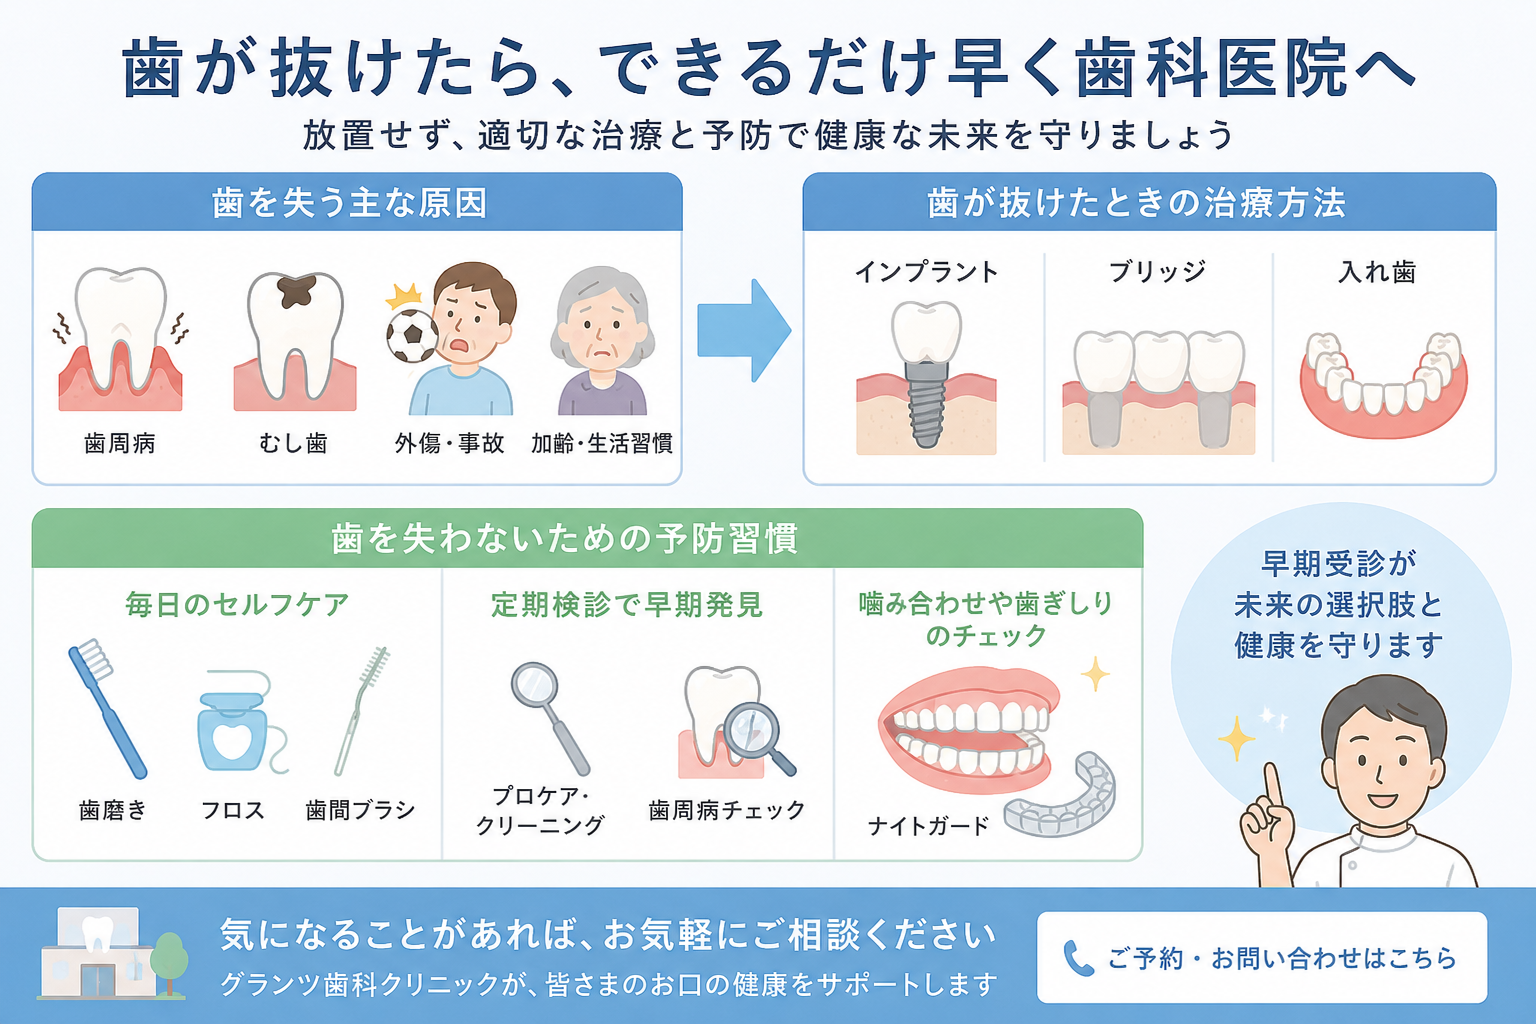

むし歯や歯周病の進行状態、歯石の有無、顎関節の状態、詰め物や被せ物の状態など多くの情報を読み取ることができます。